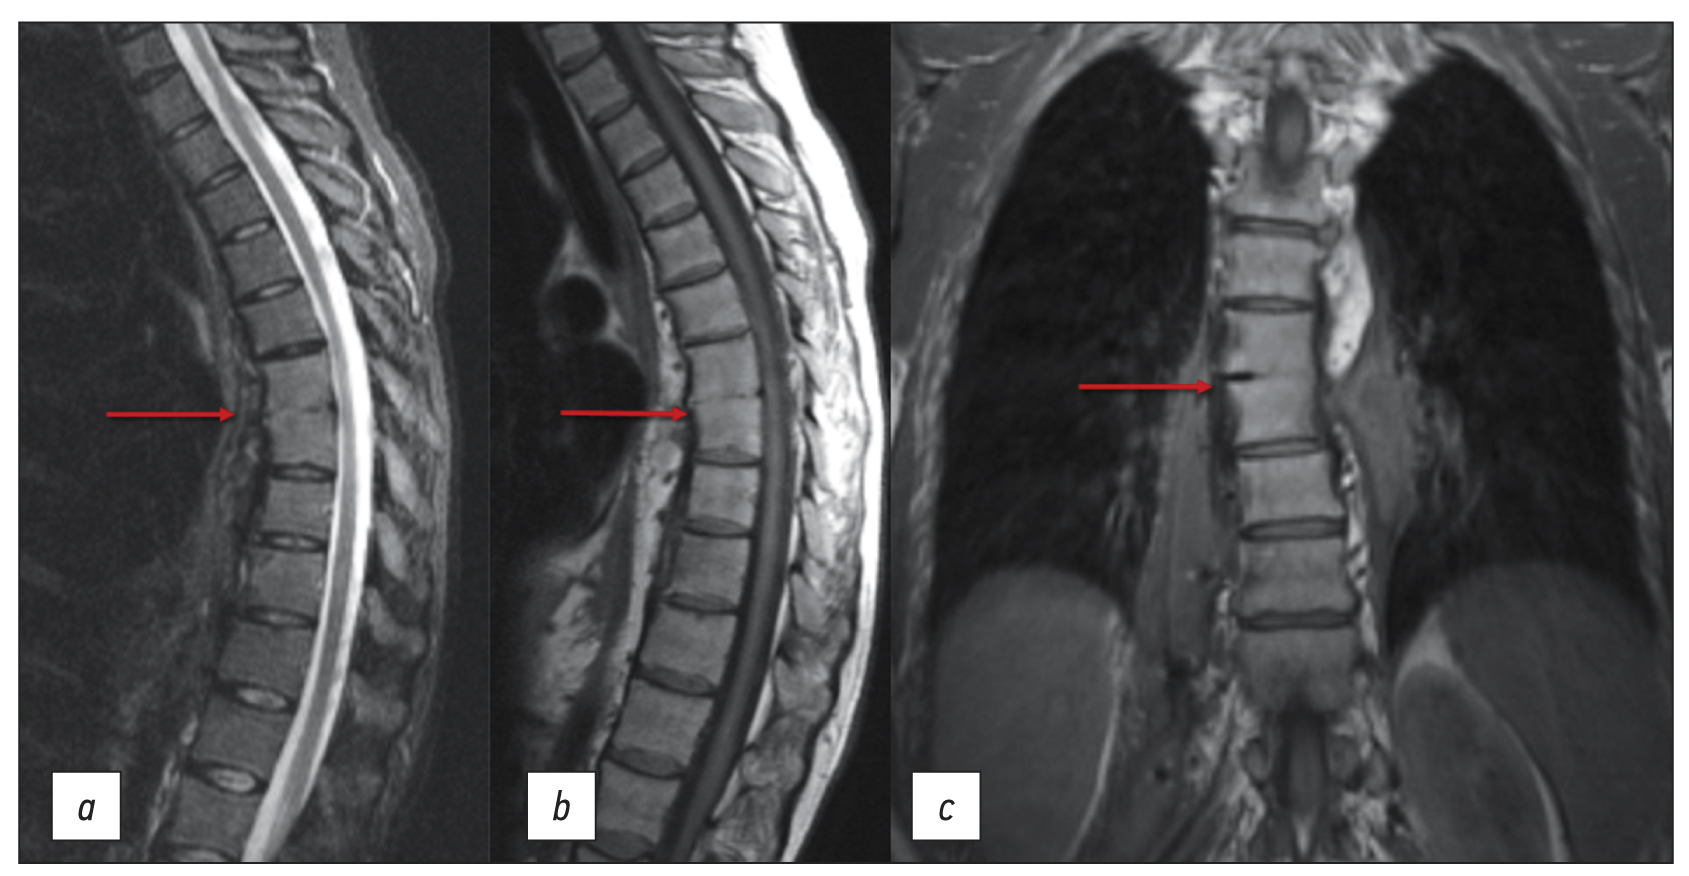

本文介绍一例因食管瘘引起的ThVII-ThVIII椎骨继发性脊椎炎的临床病例。在最初诊断时,医生认为脊椎炎与脊髓麻醉有关,而脊髓麻醉是在发病前6个月进行的,因为腰部皮肤上有瘘管缺损。这次在居住地的外科医院进行了三次手术治疗。医生最初并没有考虑到内窥镜检查结果以及病人关于进食、疼痛和瘘管分泌物性质之间关系的主诉。在额外检查的帮助下,包括口服造影剂的食道CT扫描和瘘管CT造影,确定了食管瘘的主要诊断,而胸椎脊椎炎只是次要并发症。